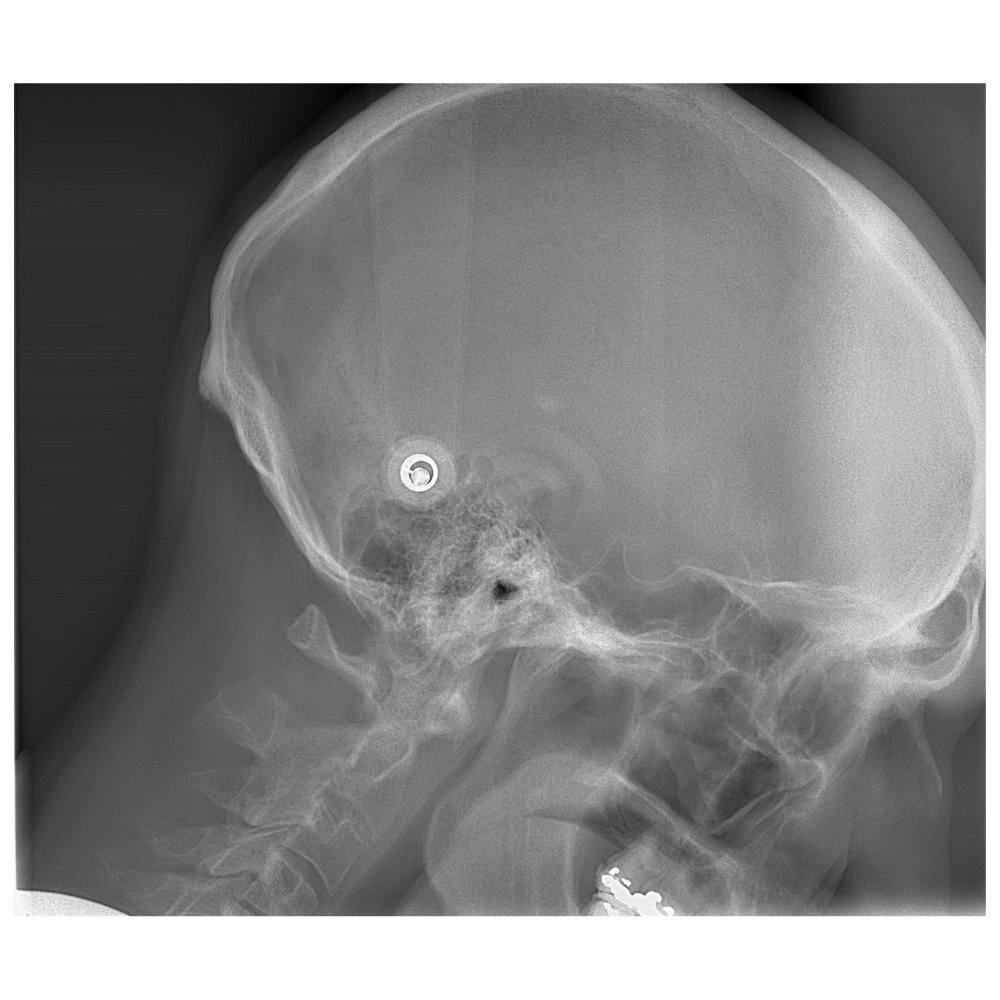

Descripción: Telerradiografía Lateral de Cráneo (Cefalometría) tomada con la cabeza del paciente en posición de flexión (inclinada ligeramente hacia adelante).

Propósito: Analiza la relación entre el cráneo, la mandíbula y, crucialmente, la columna cervical en una postura específica, buscando cómo la flexión afecta la oclusión y la ATM.

Descripción: Telerradiografía Lateral de Cráneo (Cefalometría) tomada con la cabeza del paciente en posición de extensión (inclinada ligeramente hacia atrás).

Propósito: Similar a la flexión, pero evalúa la influencia de la postura de extensión de la cabeza en la columna cervical y la mordida. Las vistas de flexión y extensión se usan para detectar inestabilidades.